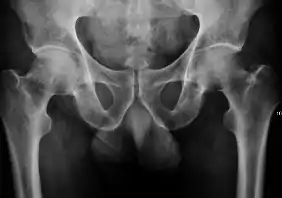

Projectional radiography ("X-ray") is the first imaging technique of choice in hip pain, not only in older people with suspected osteoarthritis but also in young people without any such suspicion. In this case plain radiography allows categorization as normal hip or dysplastic hip, or with impingement signs, pincer, cam, or a combination of both.[1]

Projectional radiography ("X-ray") is currently useful not only in older people in whom osteoarthritis of the hip is suspected but also in younger people without osteoarthritis, who are being evaluated for femoroacetabular impingement (FAI) or hip dysplasia.[1]

Plain radiography allows us to categorize the hip as normal or dysplastic or with impingement signs (pincer, cam, or a combination of both). Besides these, pathologic processes like osteoarthritis, inflammatory diseases, infection, or tumors can also be identified (Figure 1).[1]

Figure 1.

- Radiography in normal hip

- X-ray in pincer impingement type of hip dysplasia

- X-ray of cam

- Hip in osteoarthritis

- Septic arthritis